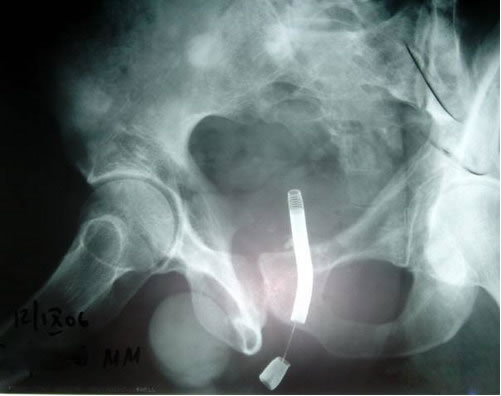

Рентгеновское изображение внутриматочной спирали: Что нужно знать